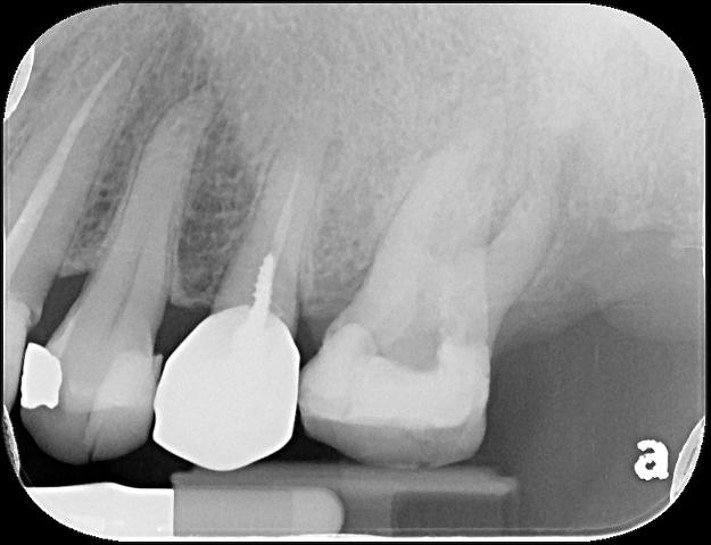

治療前,第一大臼齒根尖病變